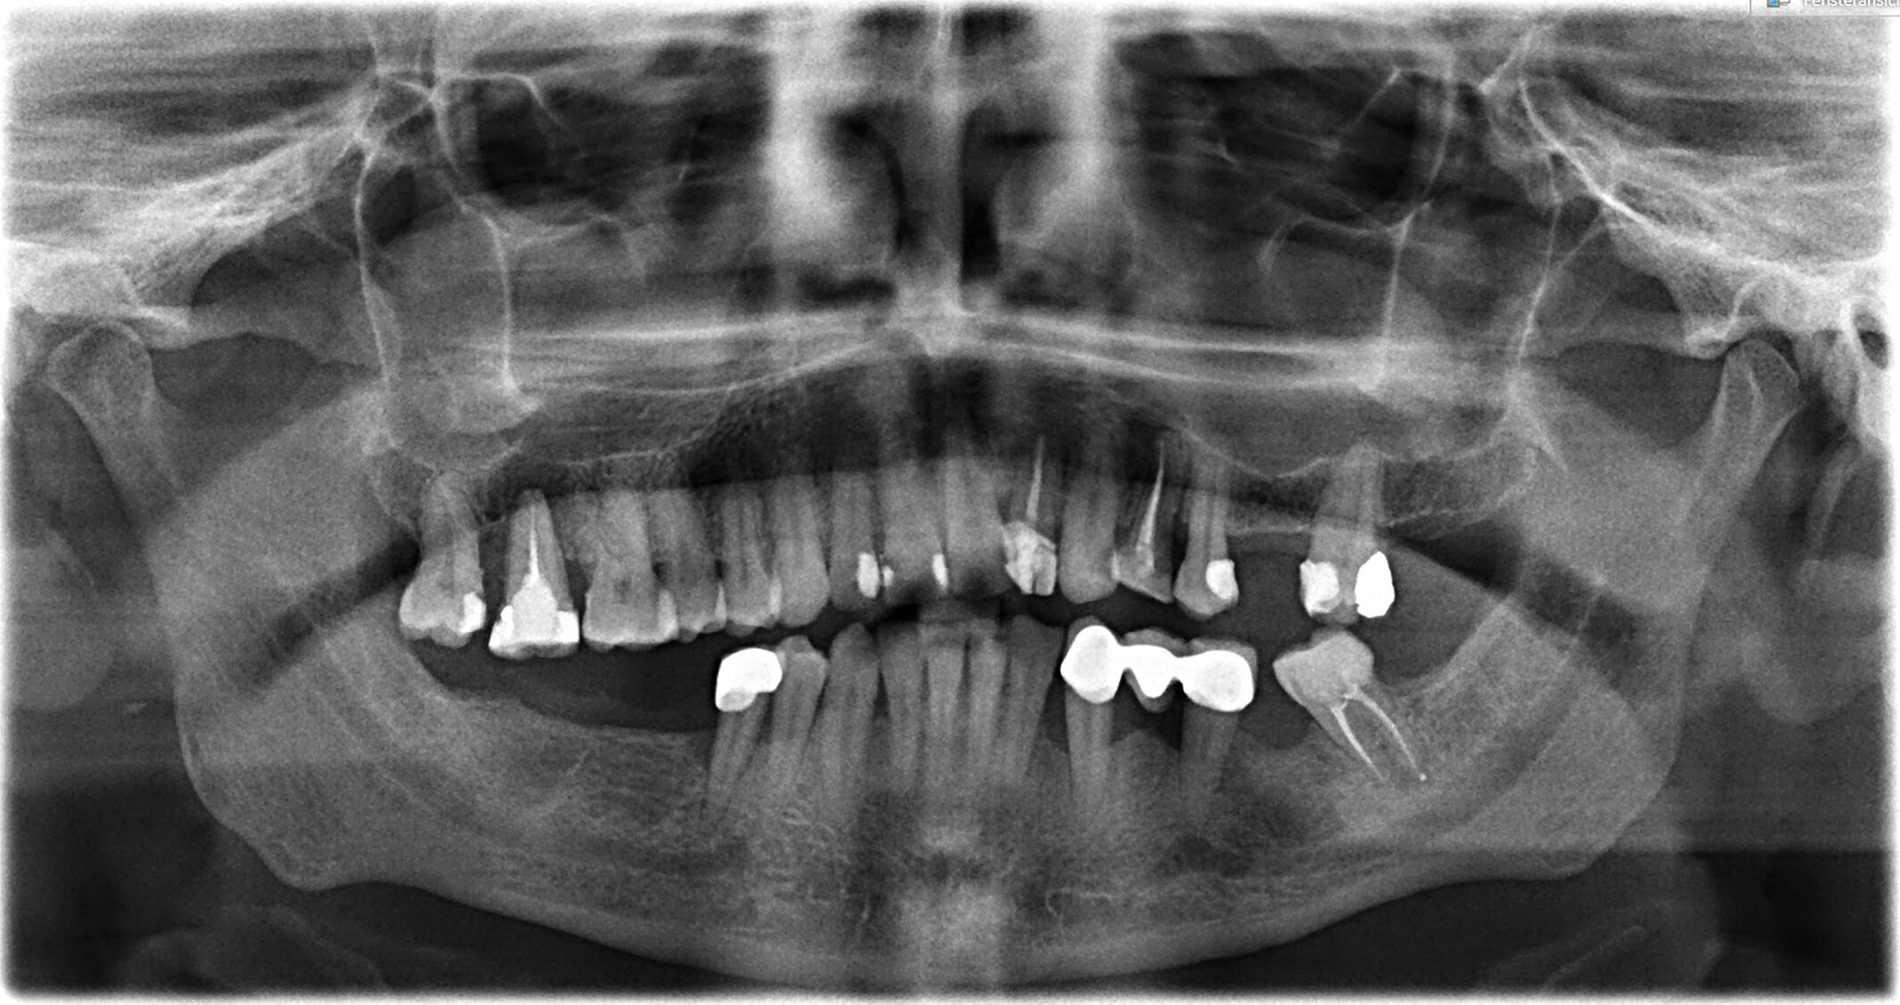

Dort wurde eine ausgedehnte apikale Läsion an Zahn 17 sowie eine kleinere Läsion an 24 festgestellt (Abbildung 2). Beide waren klinisch druckdolent. Der Patient wurde über deren notwendige Therapie aufgeklärt. Neben der Extraktion der Zähne 18 und 17 wurden die Therapieoptionen des Zahnes 24 (Revision, Wurzelspitzenresektion oder Extraktion) erläutert. Der Patient entschied sich für die Wurzelspitzenresektion und wollte den Eingriff zu einem späteren Zeitpunkt durchführen lassen. Außerdem zeigten sich im Jahr 2022 die beiden Kieferhöhlenzysten deutlich vergrößert im Vergleich zur Voraufnahme aus 2018 – eventuell als Reaktion auf die entstandene apikale Parodontitis der benachbarten Zähne. Aufgrund der infektionsabhängigen Größenveränderung wurde die Verdachtsdiagnose in „Pseudozyste" geändert. Dem Patienten wurde aufgrund der Größe die Entfernung beider Zysten zur histologischen Absicherung empfohlen. Das wollte er sich noch überlegen.